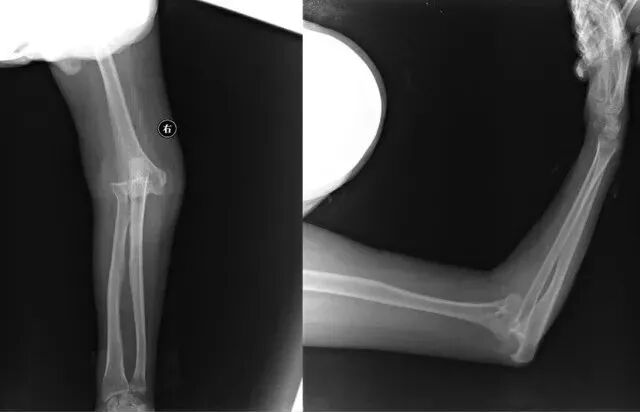

右肘关节脱位